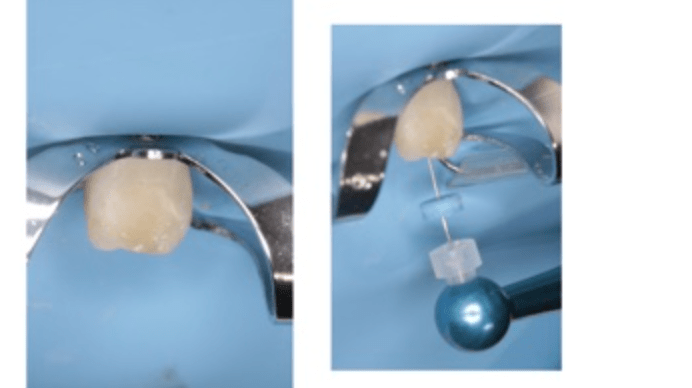

Reconstrucción preendodóntica

Reco pared vesticular

Reco pre-endo gingivectomái, pared yuxtaosea

Reco pre-endo, molar inferior

Reco preendo + 4 conductos molar superior

Reco preendo + gingivectomía

Reco preendo, 2o Molar superior